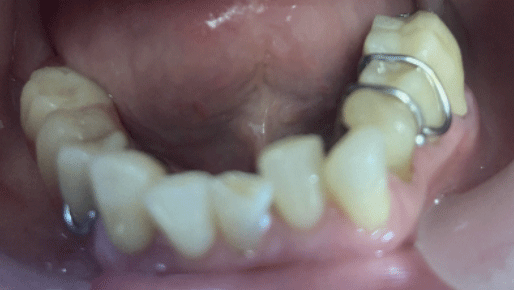

0323_Elsaraj-pic-2 alternate text for this image

Abstract This case report presents a novel intramuscular injection directed at the lateral pterygoid muscles as a potential treatment for Tinnitus in a TMD-related pain patient. The authors present a clinical case of a chronic TMD-related pain patient with chief complaints of jaw pain and tinnitus. The patient presented with additional symptoms, including ear pain, … Read more